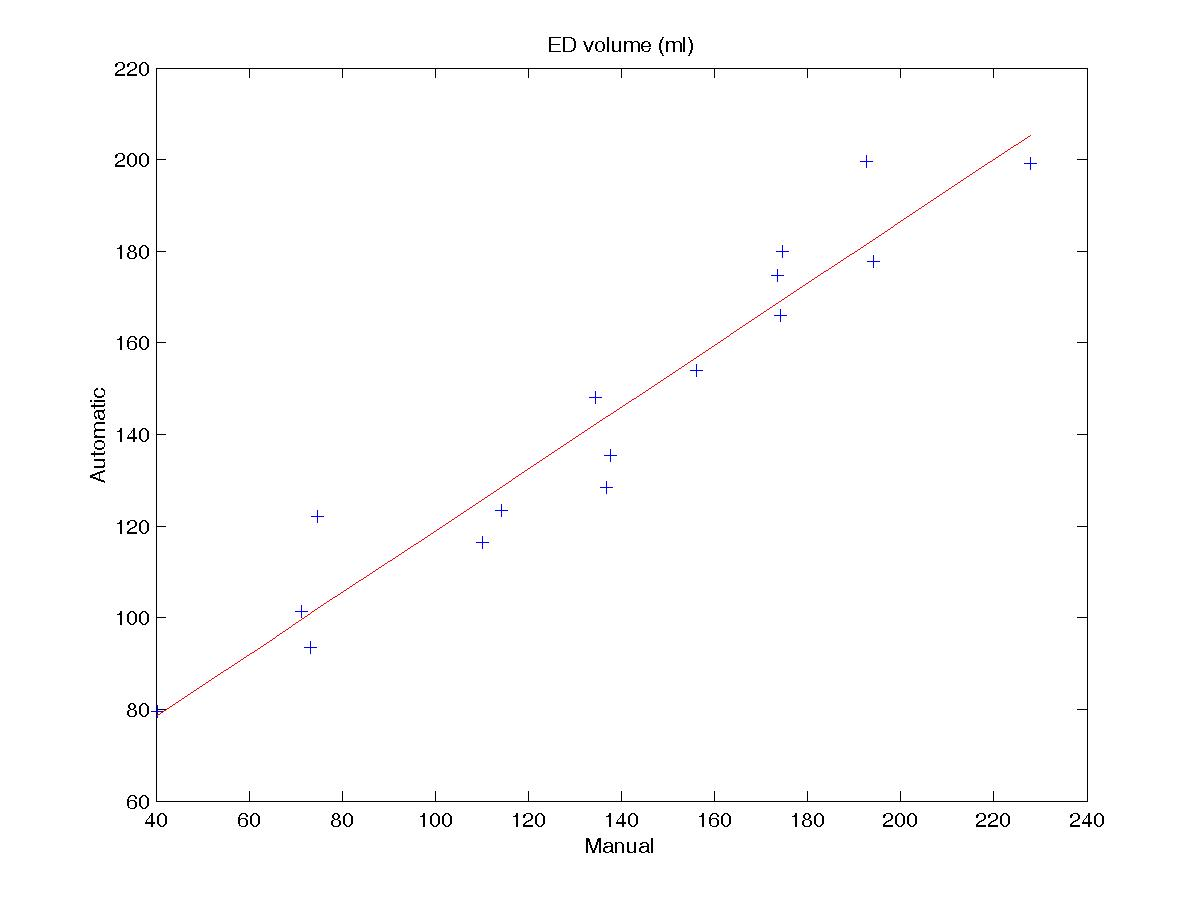

Figure 4 shows the regression plots for the endocardial volume at ED and ES. For both cases, the regression coeffictient is good (0.96 and 0.97 respectively) and the spread of the values is relatively low, demonstrating that the influence of the poor segmentation in the apical slices doesn’t have much influence in the endocardial volume estimation. Errors obtained in the computation of the ejection fraction (EF) and ventricular mass (VM), which are based on volume estimations, are reported in table 3.